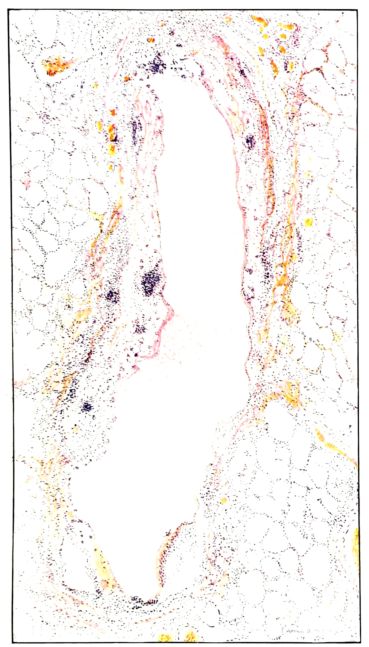

FIG. III. AUTOPSY NO. 90. DRAWING FROM A LESION OF THE TRACHEA (SOMEWHAT OLDER THAN THAT ILLUSTRATED IN FIGURE II). THE MUCOSA IS ENTIRELY LACKING. CONGESTION AND EDEMA ARE THE STRIKING FEATURES IN THE SUBMUCOSA. THE NECROTIZING PROCESS HAS EXTENDED INTO THE MUCUS GLANDS. THIS IS SHOWN IN THE LOWER PICTURE.

The changes are less marked, perhaps, in the trachea than in its finer ramifications. The mucosa is constantly more or less destroyed and large areas, usually focal, are entirely devoid of their epithelial covering. This is replaced by a sparse exudate, composed largely of red blood cells, mucus, a small amount of fibrin, and nuclear fragments (Fig. II). It may dip into the submucosa for a short distance, but usually these indentures are associated with the ducts of the mucous glands into which the inflammatory reaction extends. A more striking feature than the exudate, however, is the edema and the congestion of the submucosa. The loose areolar tissue of the submucosa is spread widely apart, and throughout it distended blood vessels are very conspicuous. Occasionally such a vessel is broken and actual hemorrhage appears in the submucosa. Occasionally, too, the inflammation extends down the duct to the mucous gland itself, and here, also, aplastic inflammatory reaction is evident, inasmuch as the acini now stain intensely red with the cells undifferentiated from each other and specked here and there by broken remains of the dead nuclei (Fig. III). After the disease has continued for a short period, even at the end of five or six days, some regeneration of the epithelial lining may be seen (3) (Fig. IV). But despite this, the acute picture persists, and there goes on, side by side, an attempted repair characterized by epithelial regeneration and the same evidence of acute change. Since the lesion is essentially a superficial one, scars or contractures of any extent are not encountered in the trachea, even in examples of the disease that have ended fatally only after many weeks.[4]